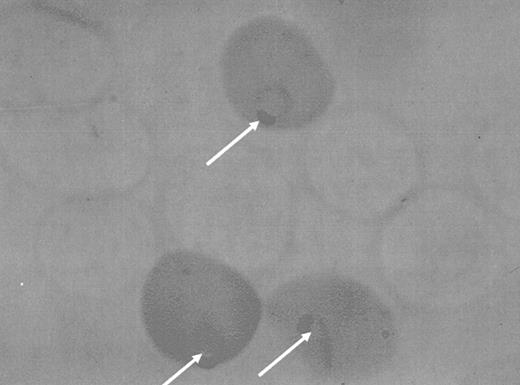

The prevalence of G6PD deficiency is very high in some parts of the world. Its distribution is largely tropical and paralleled the distribution of malaria, a disease with high morbidity and mortality, and therefore a powerful selective force in human populations. The hypothesis that this infection was responsible for a balanced polymorphism, maintaining a high frequency of G6PD-deficiency mutations as a defense against malaria, was examined in numerous epidemiologic studies in Africa and elsewhere.49,50 The most convincing evidence for an effect of G6PD deficiency on malarial infections came from ingenious observations made by Luzzatto et al.51 Since heterozygous females contained in their circulation a mixture of normal and G6PD-deficient cells, it was possible to examine the percentage of each type of cell parasitized in such individuals, and it was shown that the deficient cells were spared in comparison of the normal ones (Figure 6).

An indirect histochemical stain of erythrocytes from a heterozygote for G6PD deficiency who was suffering from naturally acquired malaria. The more pigmented cells are those that contain normal G6PD activity. They contain the highest percentage of malaria parasites, as shown by the arrows. (Courtesy Professor Lucio Luzzatto.)